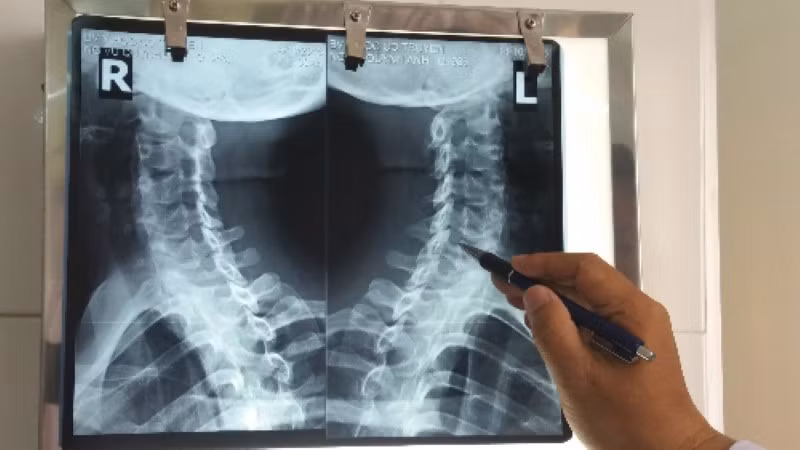

Theo chuyên gia này, để chẩn đoán bệnh thoái hoá đốt sống cổ, các bác sĩ có thể sử dụng những phương pháp như chụp Xquang, CT và MRI cột sống cổ. Đối với cận lâm sàng, có thể chụp cộng hưởng từ cột sống cổ, điện cơ hoặc xét nghiệm máu (trong trường hợp để phát hiện các dấu hiệu viêm….).